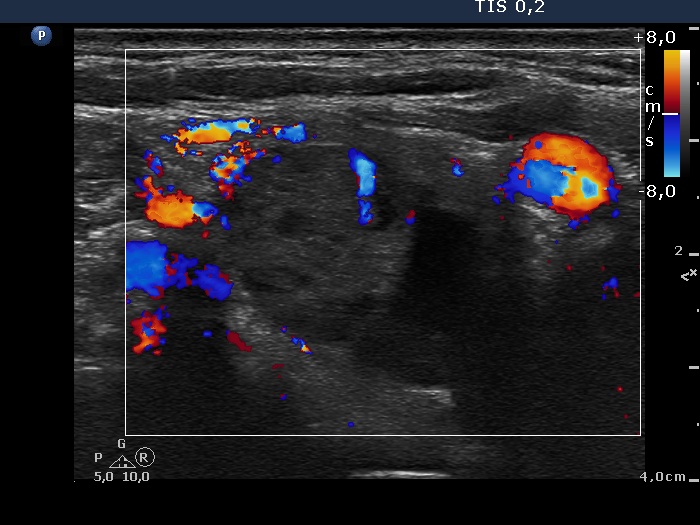

Ultrasonography: The thyroid was echonormal and intact. There was a cystic-minimally hypoechogenic mass lateral and lower to the right thyroid. The vascularization was not specific.